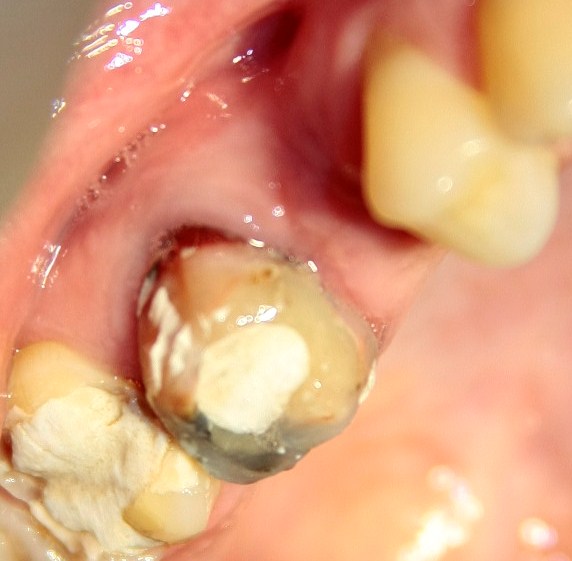

Немедленная имплантация — оптимальное решение в любой клинической ситуации